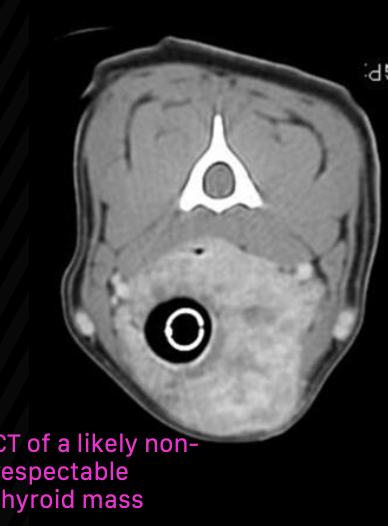

how can CT be helpful for staging/diagnosing thyroid carcinoma?

not entirely necessary, but may be useful for surgical planning of fixed/invasive tumors

also useful for radiation planning

when is surgery indicated as treatment for canine thyroid carcinoma?

surgical excision indicated when mass is freely moveable (least morbidity)